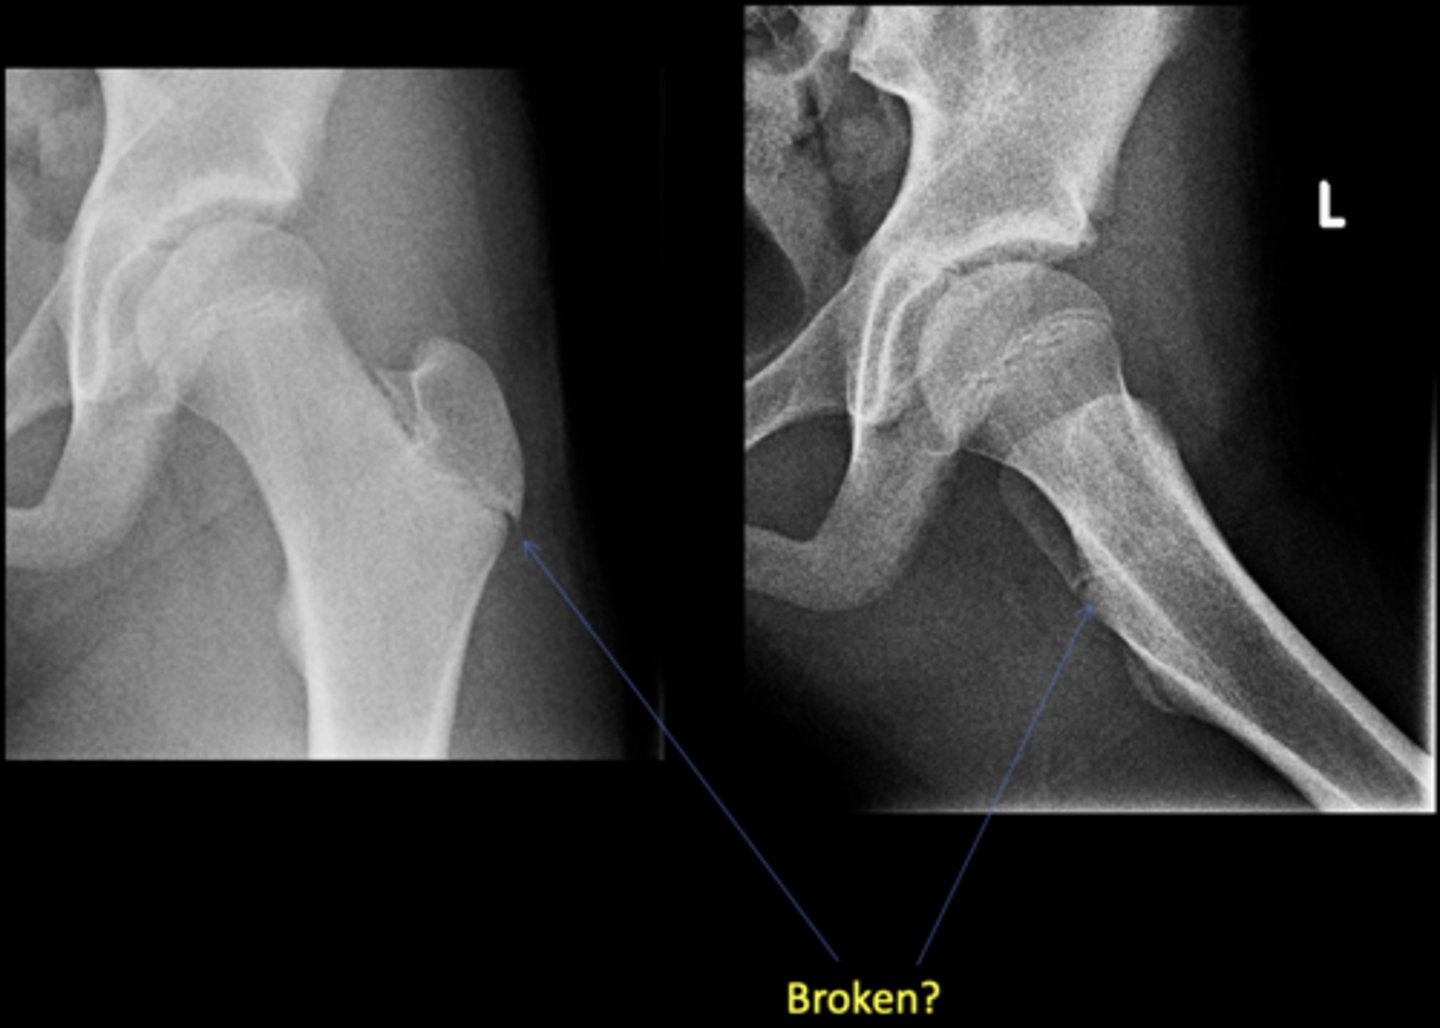

No - growth plate in a child

Broken?

<p>Broken?</p>

New cards

AP hip

View on left?

<p>View on left?</p>

23

Frog-leg hip

View on right?

<p>View on right?</p>